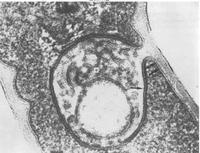

菌体大小为(0.3~0.8μm)×(1~5μm),细长稍弯,粗细不一,菌体一端或两端排列呈棒状,排列不规则,常呈L、V、X、T等字形或排成栅栏状。革兰氏染色阳性,无荚膜、鞭毛,不产生芽胞;用美兰液染色菌体着色不均匀,常呈着色深的颗粒;用奈瑟氏染色菌体染成黄褐色,一端或二端染成蓝色或深蓝色颗粒,称为异染颗粒(Metachromatic granules),其主要成分是磷酸盐和核糖核酸,是本菌形态特征之一 。

白喉棒状杆菌的菌体